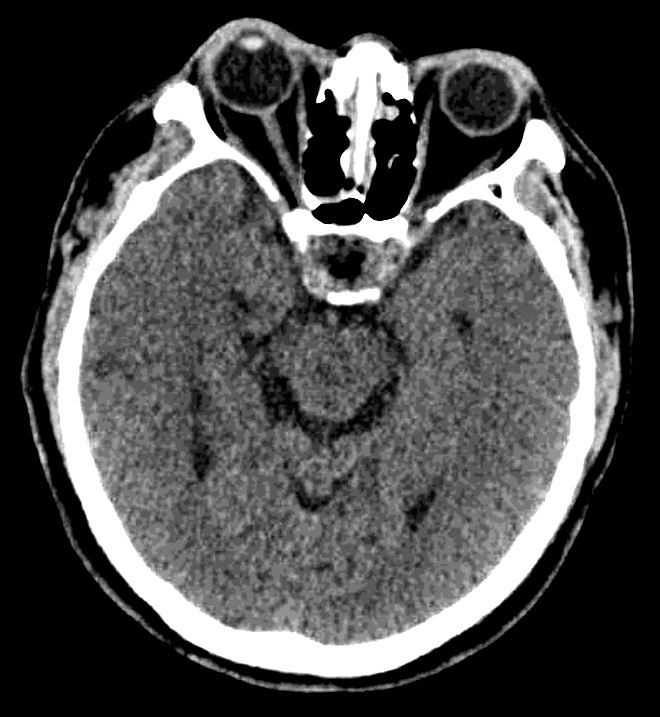

术后即可复查头颅CT示:术区干净,无出血。